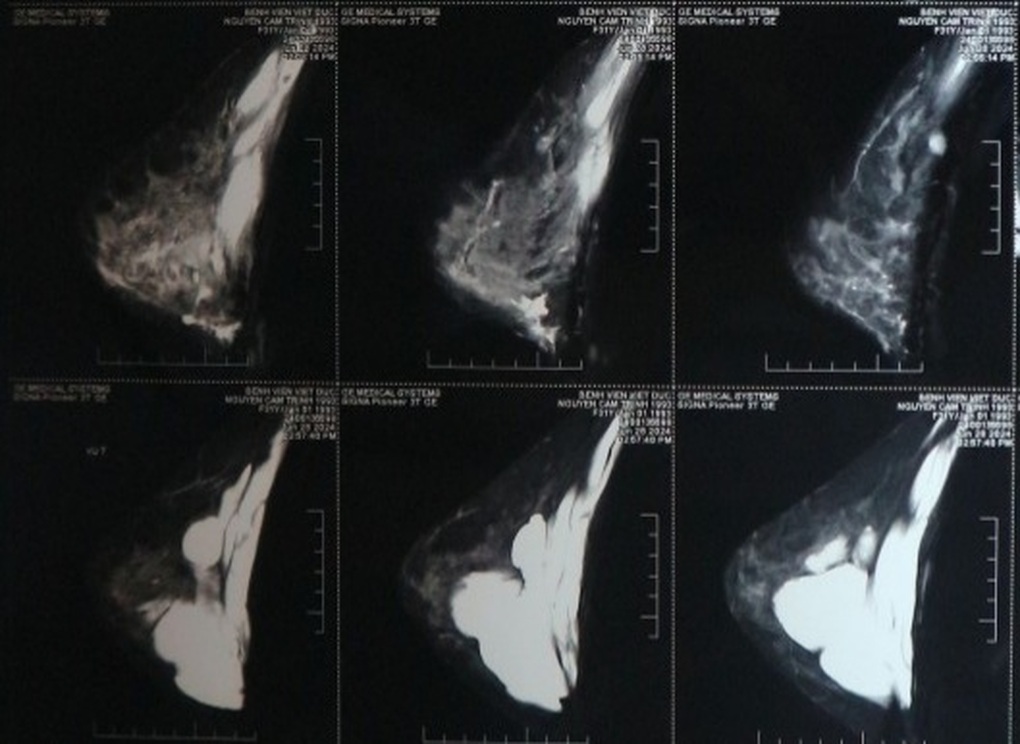

Kết quả chụp cộng hưởng từ sau đó xác định rất nhiều khối trong ngực có hình dạng như các cục "u filler" tạo thành nhiều lớp, rải rác khắp ngực cả trong tuyến vú và nguy hiểm hơn là rất nhiều vị trí trong cơ ngực lớn.

Người bệnh được chẩn đoán là áp xe ngực với các khối u filler khắp nơi nguy cơ cao do tiêm filler nâng ngực và chọc hút filler làm cho vi khuẩn ở bên ngoài đưa vào cơ thể.